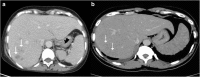

Objectives: We aim to illustrate the multimodal imaging spectrum of hepatic involvement in tuberculosis (TB). Whilst disseminated tuberculosis on imaging typically manifests as multiple small nodular lesions scattered in the liver parenchyma, isolated hepatic tuberculosis remains a rare and intriguing entity.

Methods: Indubitably, imaging is the mainstay for detection of tubercular hepatic lesions which display a broad spectrum of imaging manifestations on different modalities. While sonography and computed tomography (CT) findings have been described in some detail, there is a paucity of literature on magnetic resonance imaging (MRI) features. Due to a significant overlap with other commoner and similar appearing hepatic lesions, hepatic tuberculosis is often either misdiagnosed or labelled as indeterminate lesions. This article is a compendium of cases highlighting the spectrum of imaging patterns that can be encountered in patients with isolated primary hepatic tuberculosis as well as disseminated (secondary) disease. Rare patterns of primary disease such as tubercular cholangitis, hypervascular liver masses, and those with vascular complications are also illustrated and discussed.

Teaching points: • Hepatic TB has myriad imaging manifestations and is often confounded with neoplastic lesions. • Imaging patterns include miliary TB, macronodular TB, serohepatic TB and tubercular cholangitis. • Concurrent splenic, nodal or pulmonary involvements are helpful pointers towards the diagnosis. • Miliary calcifications along the bile ducts are characteristic of tubercular cholangitis. • Histological/microbiological confirmation is often necessary to confirm the diagnosis.